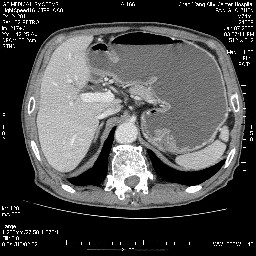

女,74岁,呕吐10余日

十二指肠降段扩张,水平段狭窄成鼠尾状,肠壁明显增厚,胰腺勾突增大成不均匀强化,其内可见低密度区,胆囊增大,1十二指肠水平段腺癌侵犯胰腺勾突可能大,2胰腺癌侵犯十二指肠(只有胆囊增大没有肝内外胆管扩张不好解释)代除外.

十二指肠降段扩张,水平段狭窄成鼠尾状,肠壁明显增厚,胰腺勾突增大成不均匀强化,其内可见低密度区,胆囊增大,1十二指肠水平段腺癌侵犯胰腺勾突可能大,2胰腺癌侵犯十二指肠 。

今日手术结果:胰腺钩突癌侵犯十二直肠,腹腔淋巴结转移.